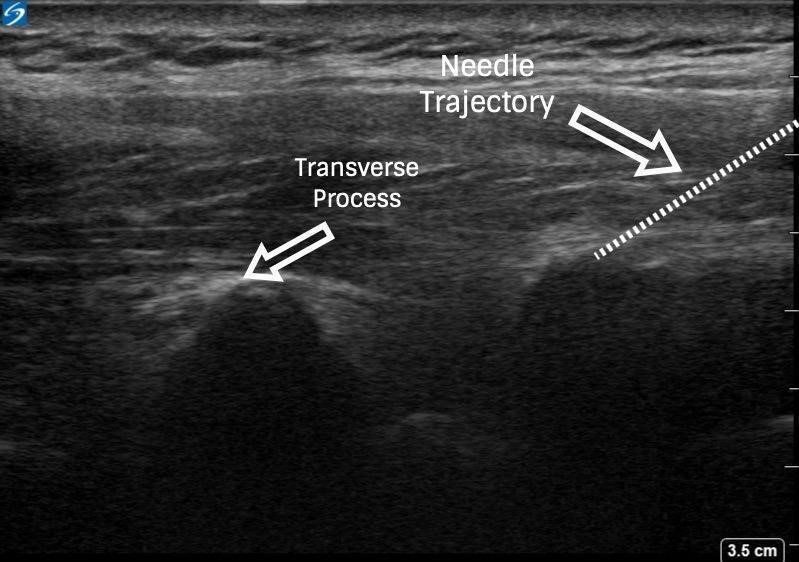

With PVB, deposit local anesthetic between the pleural and costotransverse ligament under ultrasound guidance using either an in-plane or out-of-plane needle approach. For the out-of-plane technique, hold the transducer (linear or curvilinear, depending on the patient’s body habitus) in the sagittal plane, allowing for a linear needle trajectory perpendicular to the skin (Figure 3). The pleura is visible in that plane between the ribs laterally and the transverse processes medially. In the transition from rib to transverse process, the bone image appears larger and squarer as the transducer is moved more medially (Figure 4). Hydrodissect with sterile saline to estimate the needle tip location when using an out-of-plane technique, with the downward/anterior bowing of pleura, or loss of reflection of saline upward/posterior, indicating injection into the paravertebral space. This is the preferred regional anesthetic technique at our institution and has provided effective surgical anesthesia for a variety of oncologic breast and thoracic procedures.

Figure 4: Ultrasound images of paravertebral block via out-of-plane technique

Since the ESPB was first described, the number of clinical scenarios that might benefit from it has increased exponentially. The ESPB consists of an injection of local anesthetic between the erector spinae muscles and transverse processes of the desired vertebrae. The mechanism of analgesic effect for the ESPB is somewhat unclear and may be related to either anterior diffusion to spinal nerve roots or lateral spread to intercostal nerves.[7] Similar to PVB, ESPBs can be performed with needle insertion in or out of plane relative to the ultrasound probe and with single or multiple injections (Figure 6). With an ESPB, the needle target is posterior to the transverse process itself, and the presence of this bony impediment should minimize the risk of inadvertent pleural puncture. To provide maximal analgesic efficacy, local anesthetic is visualized layering beneath the erector spinae muscle.

With the patient seated, apply standard ASA monitors, administer supplemental oxygen, and initiate intravenous fluid administration. Sedation generally includes midazolam (2 mg) and/or fentanyl (50–100 mcg). Following sterile prep, position the ultrasound probe in the sagittal plane adjacent to the planned vertebral level approximately 3 cm off of the midline of the spine (Figure 3). Scanning from medial to lateral, first identify the transverse process and rib, taking note of their transition by change in shape and depth (Figure 4). Both structures will be seen in cross-section with pleura located anterior to the cephalad and caudad bony structures. Targeted injections should occur after the transition from rib to transverse process (the transverse process is located more medially and appears more squared-off in appearance).

Taking note of the depth of the pleura, center the structure on the ultrasound screen and anesthetize the patient’s skin with lidocaine lateral and adjacent to the middle of the probe. The costotransverse ligament is located posterior to the pleura (occasionally difficult to visualize on ultrasound imaging) and injections in the space between the costotransverse ligament and pleura should provide effective PVB. Insert the block needle approximately 1–2 cm less before the pleura using the depth indicators on the nerve block needle. The local anesthetic for the block and a syringe of sterile saline are attached to the block needle via a three-way stopcock, initially open to saline and previously flushed with saline to remove all air. Give a small but firm push of the saline flush to provide an estimation of needle tip position. Advance the needle in small increments until the saline is no longer seen reflecting superficially from the pleura. Placing the needle tip in the paravertebral space will result in anterior pleural deflection in a bowing-like manner and can usually be visualized spreading superiorly and inferiorly in adjacent paravertebral spaces. Skip one or two levels between injection points, depending on the incision site (eg, SLNB in axilla), tumor location, or patient anatomy.